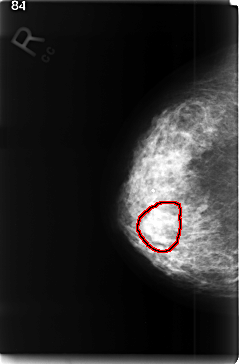

RIGHT_MLO LINES 4608 PIXELS_PER_LINE 3096 BITS_PER_PIXEL 12 RESOLUTION 50 OVERLAY

FILE: C_0350_1.RIGHT_MLO.OVERLAY

TOTAL_ABNORMALITIES 1

ABNORMALITY 1

LESION_TYPE MASS SHAPE LOBULATED MARGINS ILL_DEFINED

ASSESSMENT 4

SUBTLETY 2

PATHOLOGY MALIGNANT

TOTAL_OUTLINES 1

BOUNDARY